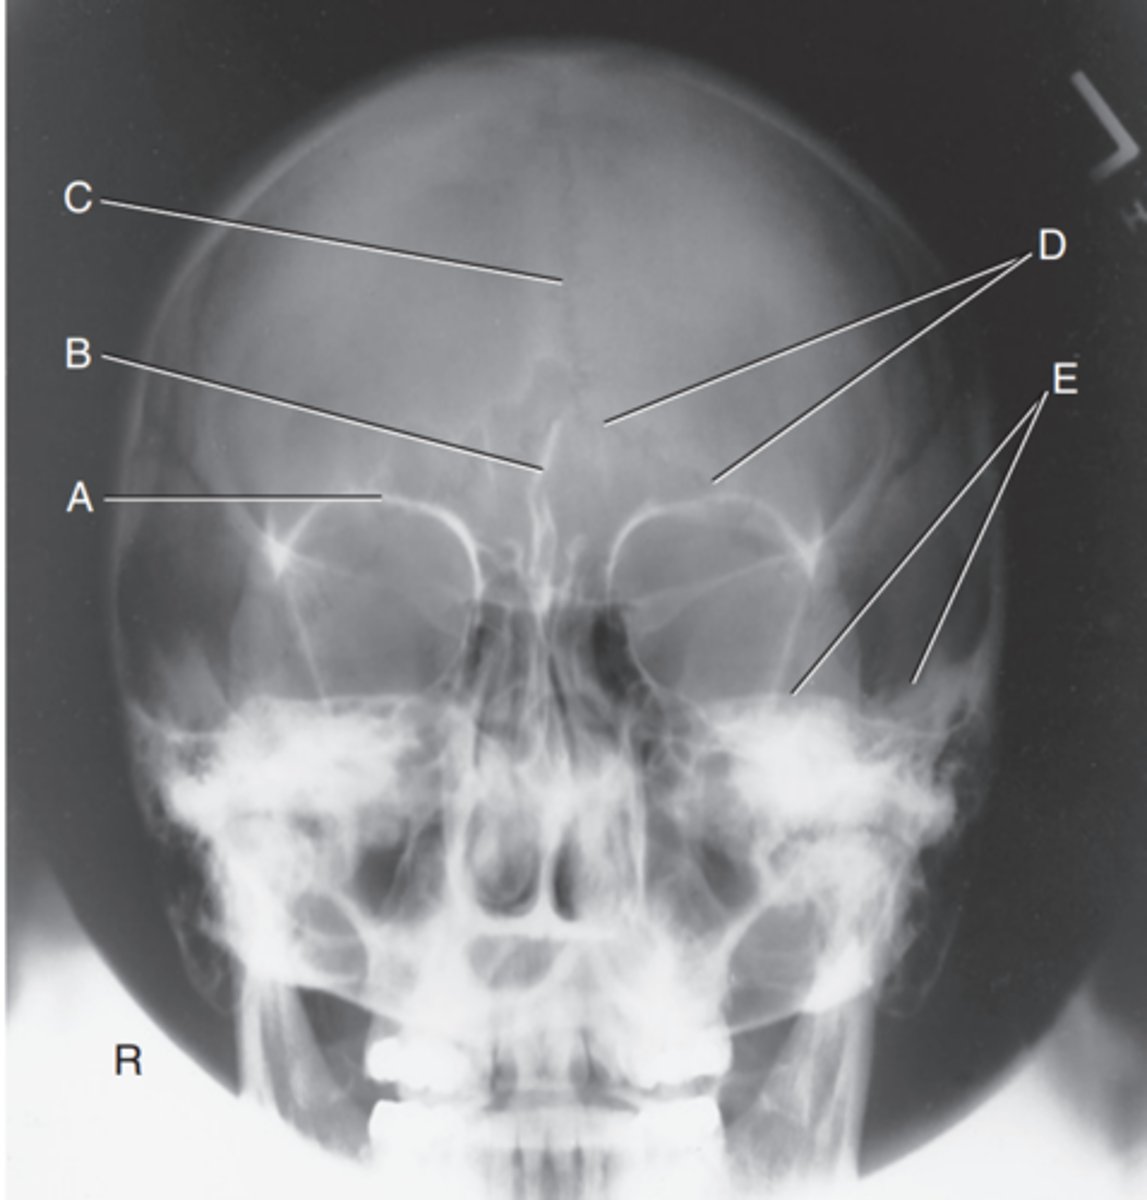

Supraorbital margin of right orbit

Label A

Crista galli of ethmoid

Label B

Sagittal suture

Label C

Lambdoidal suture

Label D

Petrous ridge

Label E